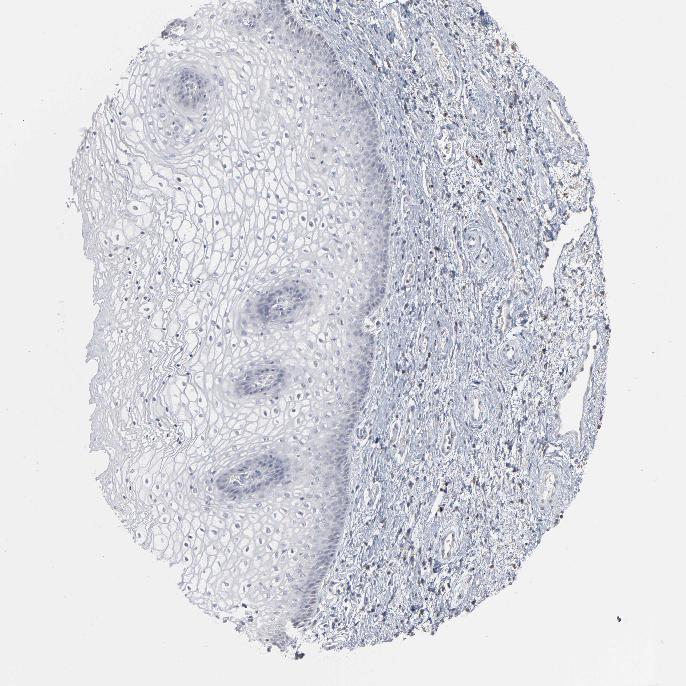

VAGINA - Antibody stainingi

Antibody staining in the annotated cell types in the current human tissue is reported as not detected, low, medium, or high, based on conventional immunohistochemistry profiling in selected tissues. This score is based on the combination of the staining intensity and fraction of stained cells.

Each image is clickable and will lead to virtual microscopy that enables deeper exploration of all samples and also displays staining intensity scores, fraction scores and subcellular localization as well as patient and tissue information for each sample.

Antibody HPA003663

Squamous epithelial cells Not detected